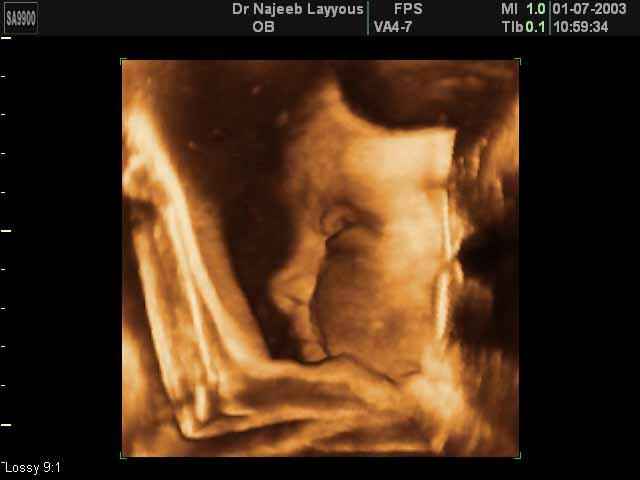

- صور لأعضاء الجنين

- صور لأطراف الجنين